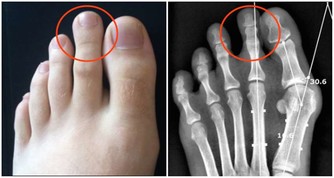

5、咯血

肺結核,支氣管擴張導致咯血患者,緊張的胸腔,腹腔壓力突然升高,血管壁破裂,造成大咯血。